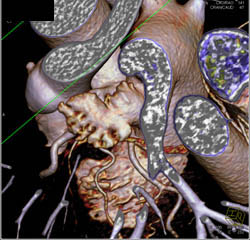

Normal LAD and Circumflex in 3D